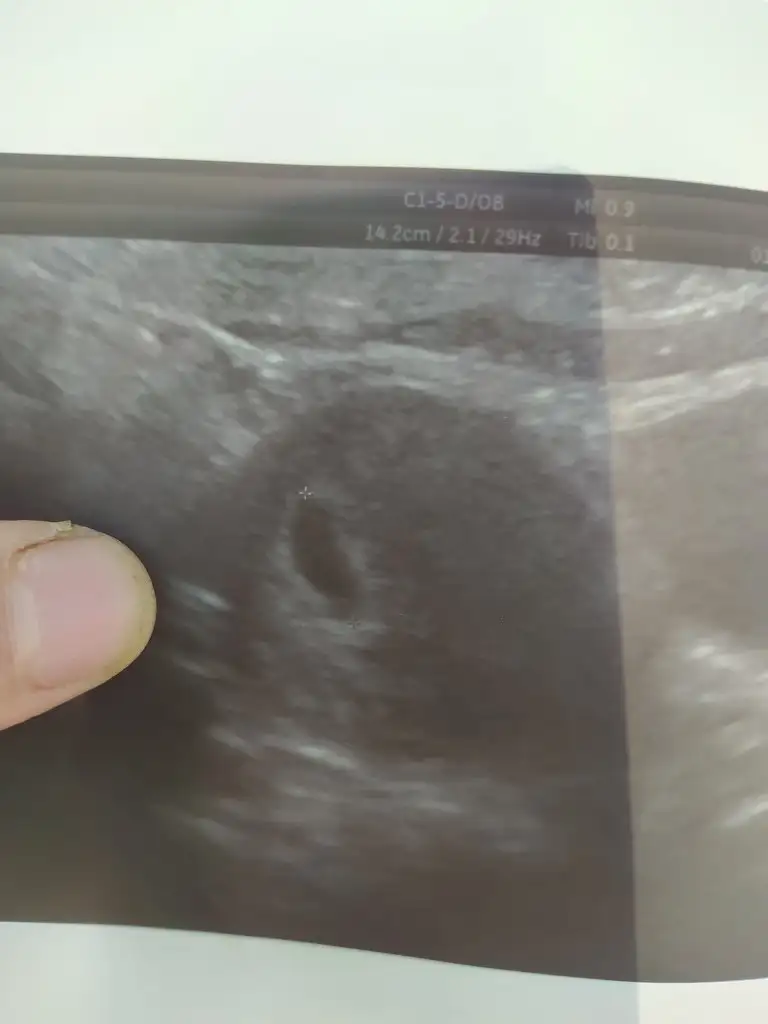

Bende ilk ultrason muayenesi oldun nasip olursa kasima anne adayiyim. Kese gordu ama bebek yok 6+6 dayiz ama bebek olusuma baslamis cikintisi var dedi

Kese boyu kaç çıktı acaba? Ben de bugün gideceğim 6+3üm. Keseyi geçen hafta götürmüştük, bu hafta bebeği ve kalp atışını görmek için çağırdı da

Bende salı keseyi gördüm 10 mmdi 15 gün sonra gel dedi doktor inşallah görürüm bebişi